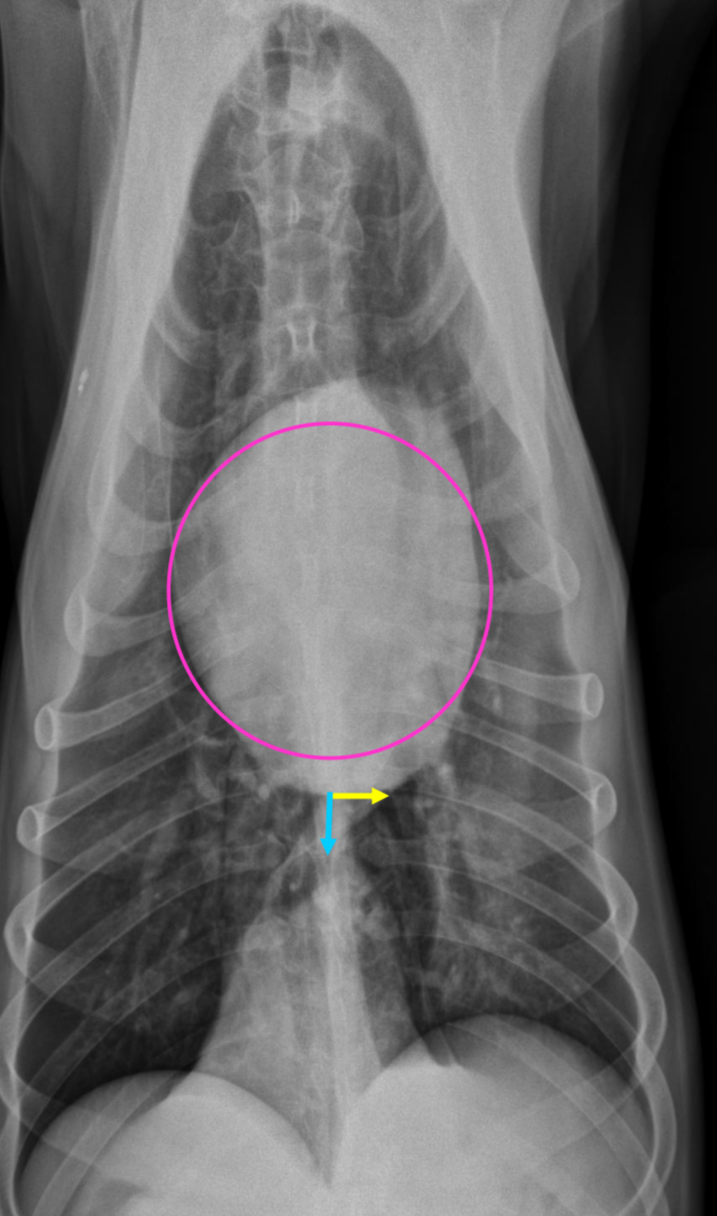

3 features of LVE VD

-elongation of cardiac silhouette

-deviation of apex to the left

-bulge at 3-5 o’clock

What part of the heart is enlarged?

LVE

3 features of LAE on DV

-double opacity sign

-separation of main stem bronchi

-LA bulge at 2:30-3 o’clock

What part of the heart is enlarged

LAE